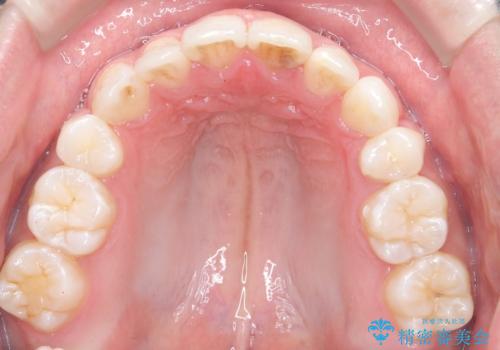

- 前歯が出ていることを主訴に来院されました。

臼歯関係が上顎前突傾向のため、上顎小臼歯を抜歯してインビザラインにて治療を行いました。

臼歯の咬合を作るために治療終盤ではゴムかけを行なっています。